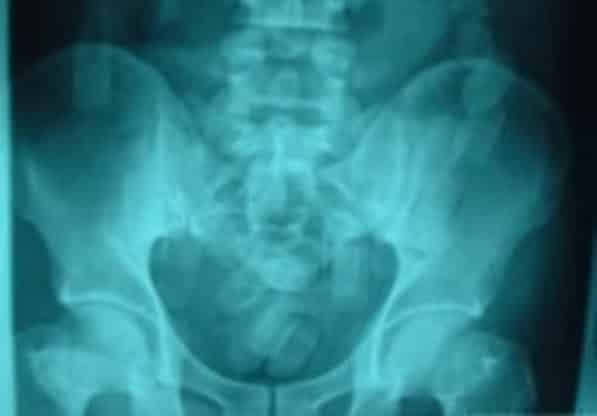

ב-30 ביוני טס קאנו מניגריה לישראל דרך אדיס אבבה שבאתיופיה, שם בלע לכאורה 77 אריזות קוקאין מנוילנות, במשקל של קילו נטו. עם נחיתתו בנתב"ג עם בתו בת ה-15, עלה כלפיו חשד, וקאנו נלקח לבית החולים, שם עבר צילום CT שגילה את "הגופים הזרים", אותם פלט בהמשך. בחקירתו הודה קאנו, המיוצג על ידי עו"ד דוד בוחבוט, והסביר כי התפתה לעשות את המעשה נוכח מחלת אשתו והצורך בכסף.